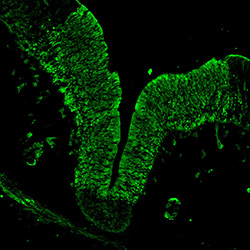

An anatomical analysis of the developing human midbrain from 6 post-conceptional weeks (PCW) to 22 PCW reveals increased tissue complexity, characterized by the emergence of dopaminergic nuclei, as highlighted by immunofluorescence analysis for tyrosine hydroxylase (TH).

MAP2

7PCW human midbrain

TH